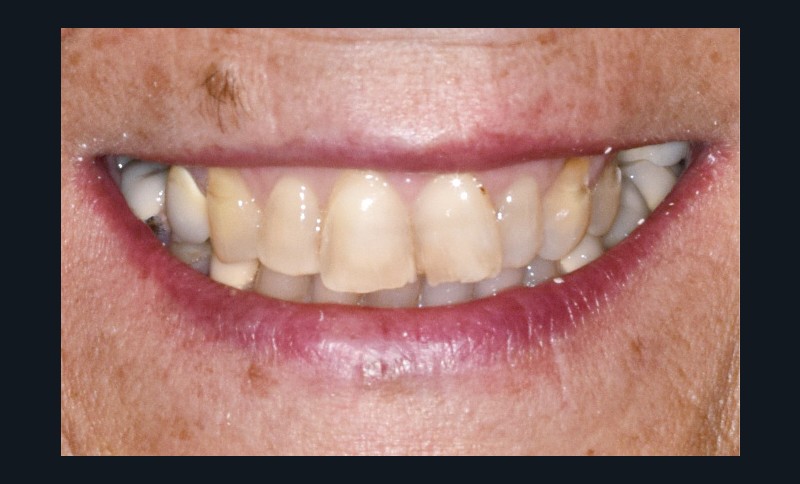

Une patiente d’une cinquantaine d’années consulte pour refaire sa prothèse amovible partielle métallique maxillaire, source d’inconfort (fig. 1 et 2).